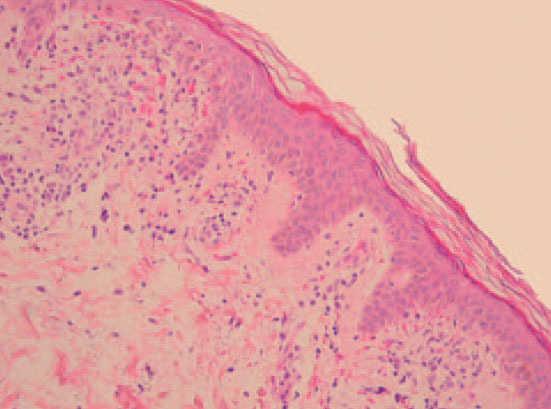

Se realizó biopsia en sacabocados (punch) de una de las lesiones anulares para estudio histológico (fig. 3).

Fig. 3.—Histología de una de las lesiones. (Hematoxilina-eosina, ×100.)

Con microscopia óptica se observaba una dermatitis perivascular superficial de predominio linfocitario con daño liquenoide focal de la interfase dermoepidérmica, abundantes hematíes extravasados y presencia de algunos siderófagos.